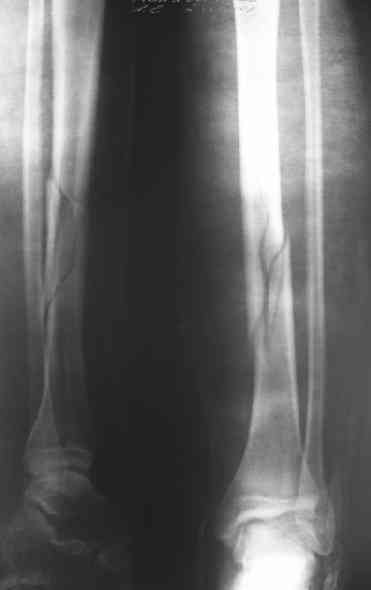

Вчера первый раз синтезировали голень гвоздем Fixion.

Спиральный оскольчатый перелом, ниже середины, у молодого парня. Сделали "классический" вариант гвоздя, который еще без винтов. Получилось все легко. Не торопясь, сделали операцию минут за 20. См. фото.

Дорогой Александр. Имею скромный опыт использования системы Fixion при переломах плеча, бедра и тибии. Всего 18 наблюдений с сентября 2006 г. Результаты отличные. Гвоздь индивидуален для каждого медуллярного канала. Легко имплантируется как в узкий, так и в деформированный канал. Это позволяет применять метод интрамедулярного остеосинтеза без ненужных потерь времени операции, флюороскопии и реально снижает крвопотерю и операционный риск. Удаление происходит без проблем. Особенно интересны больные с ипсилатеральными переломами бедра и голени.

В отношении ранней нагрузки при спиральных переломах лучше не торопиться. По данному случаю необходимо достигнуть исчезновения щели между штифтом и внутреним кортексом по Rg. А так картинка прекрасная - и длина сегмента и репозиция. Можно поздравить, коллега!